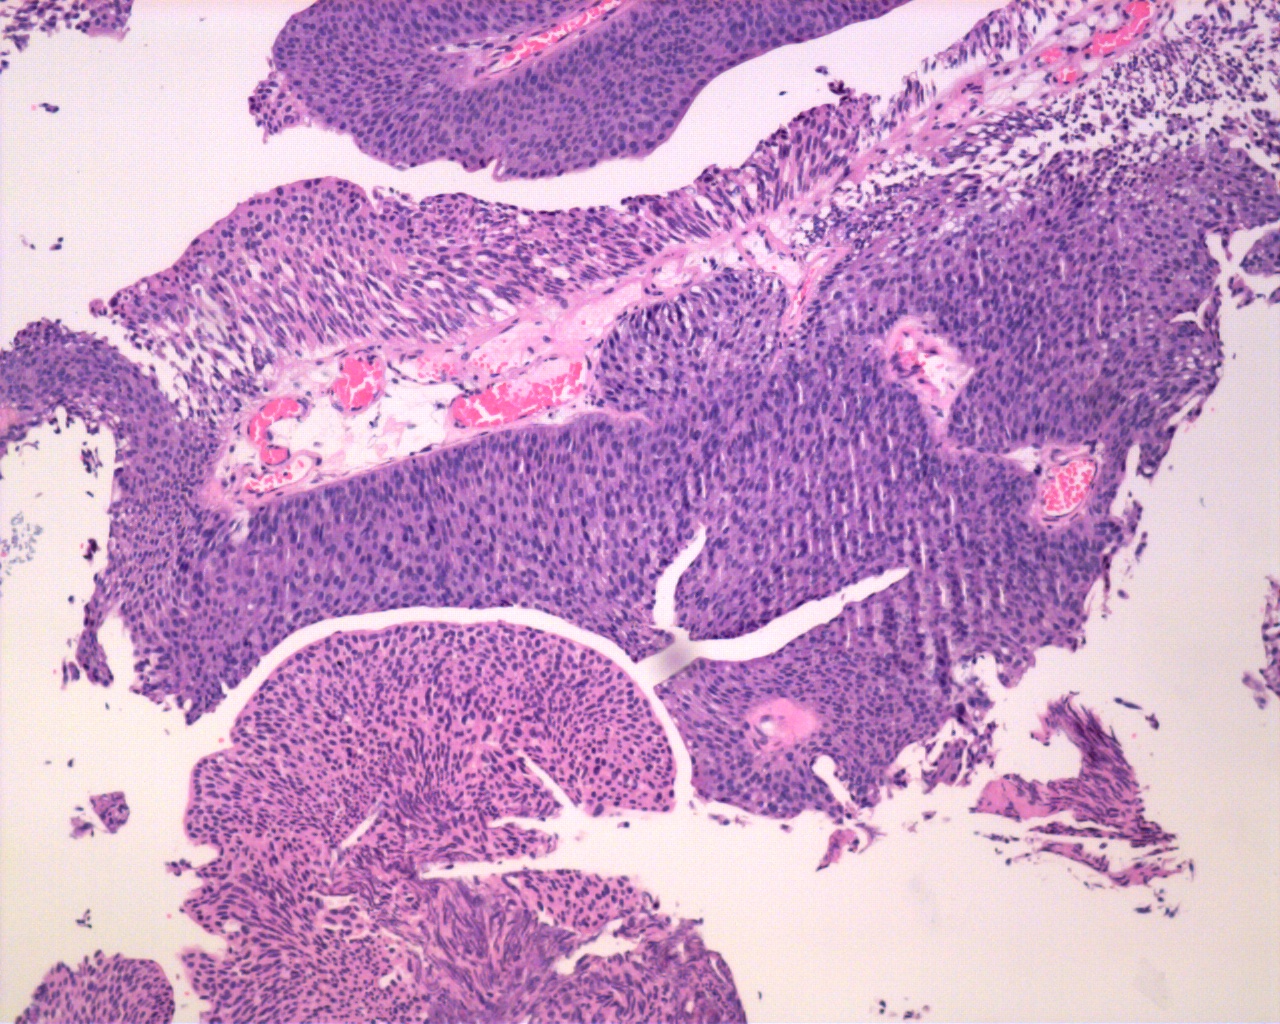

Consensus grade: Low-grade papillary urothelial carcinoma (LG-PUC)

Case description (by case creator):